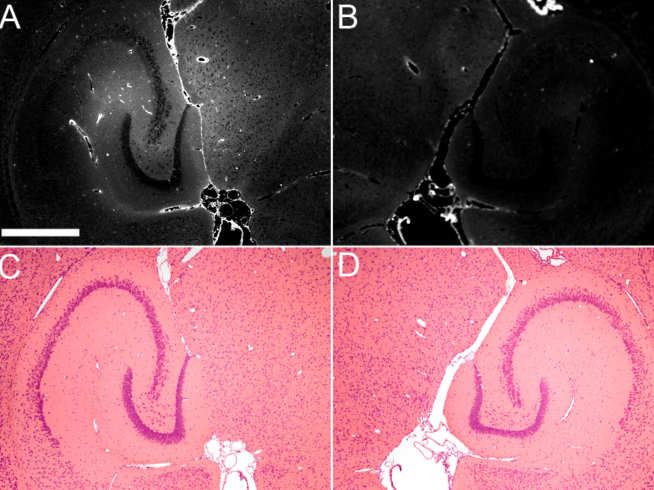

The student will design, construct, and characterise a non-invasive ultrasound-based technology that drives systemically administered microbubbles into volumetric oscillations. This technology exerts mechanical stress from within the capillaries to increase permeability and allow drugs safe passage into the brain. The student will then use this technology to deliver drugs in transgenic AD mice, reduce AD pathology, and improve cognitive function.